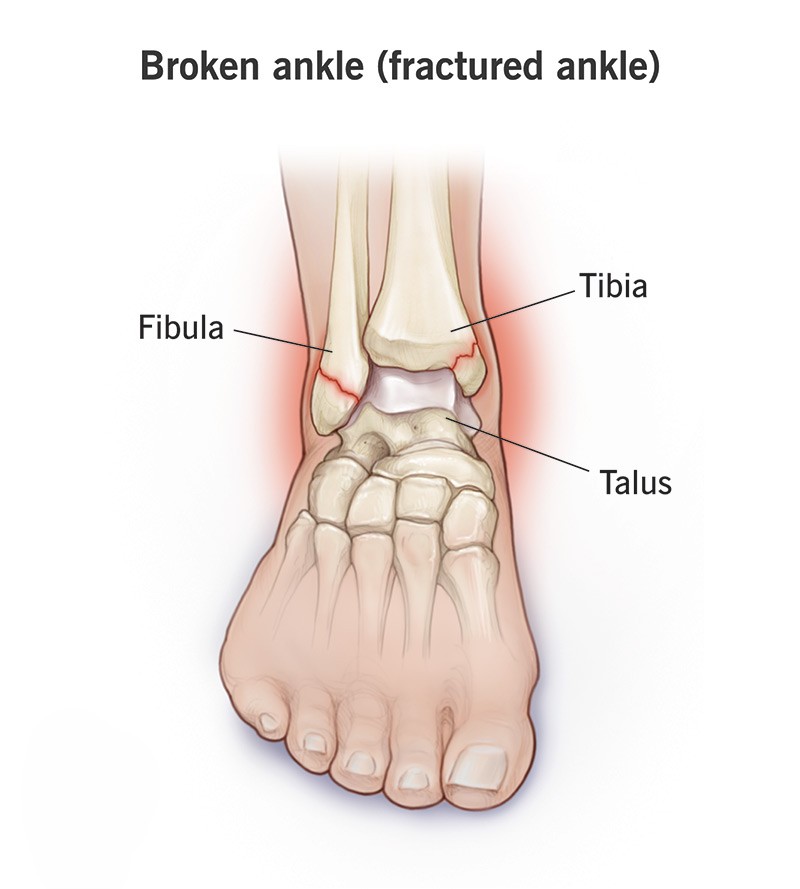

足踝骨折是指腳踝的骨頭出現裂開或斷裂的情況。常見症狀包括劇烈疼痛、明顯腫脹、瘀青、無法負重行走,嚴重時可能出現變形。

常見的足踝骨折情況,例如跌倒時腳踝受力過大、運動期間撞擊或扭傷、交通意外或高處墜落,都可能導致骨頭斷裂。